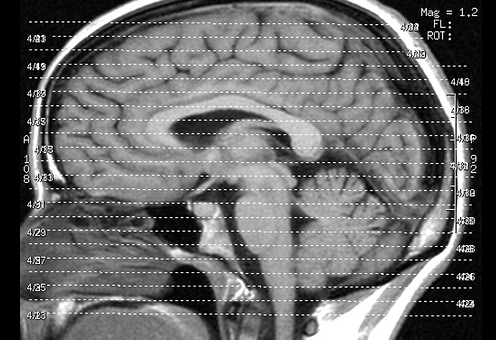

Dabei stellten die Forscher fest, dass strukturelle Veränderungen in bestimmten Hirnregionen mit den Veränderungen des IQ korrelierten. Veränderte sich der verbale IQ hing das zusammen mit Veränderungen einer Hirnregion, die während des Sprechens aktiviert wird. Veränderungen des nonverbalen IQ hingegen hängen zusammen mit einer Gehirnregion, die mit den Bewegungen der Hand in Zusammenhang gebracht werden.